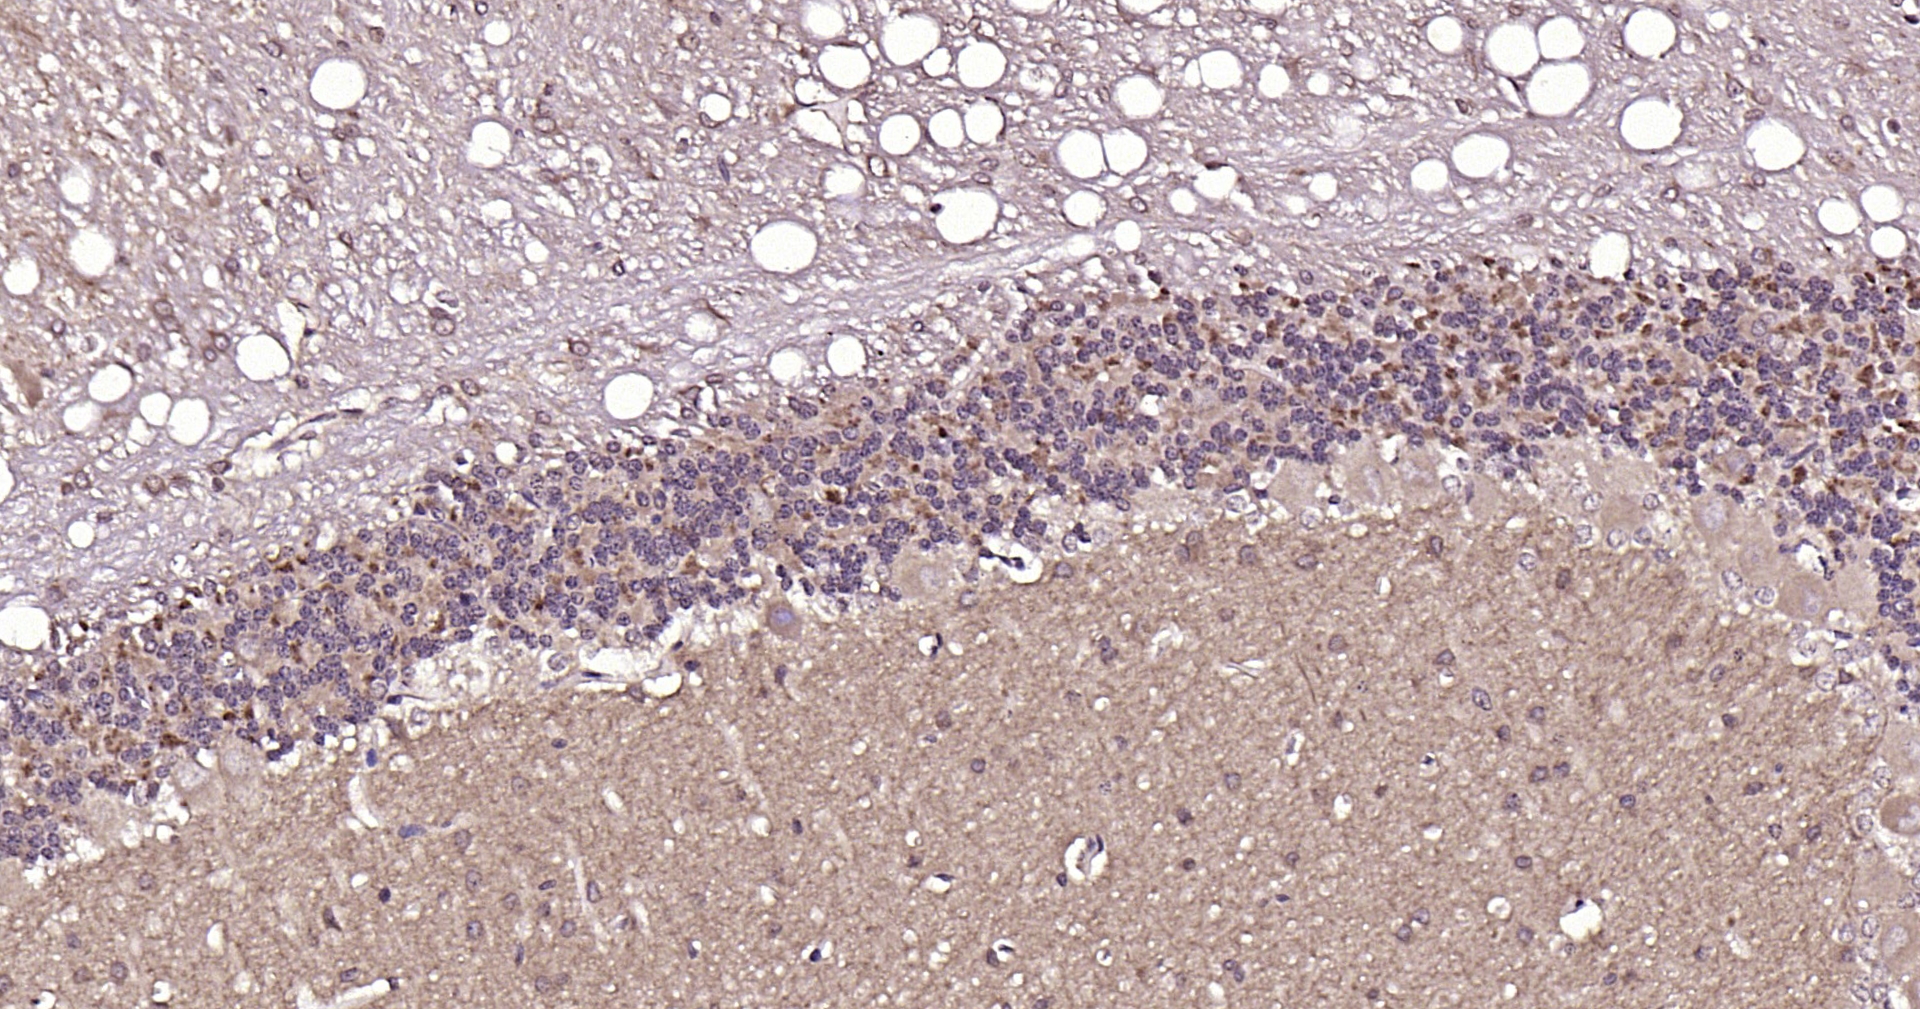

VGLUT1/BNP1 Polyclonal Antibody

• IHC-P

• IHC-F

IHC-P IHC-P=1:100-500

IHC-F IHC-F=1:100-500